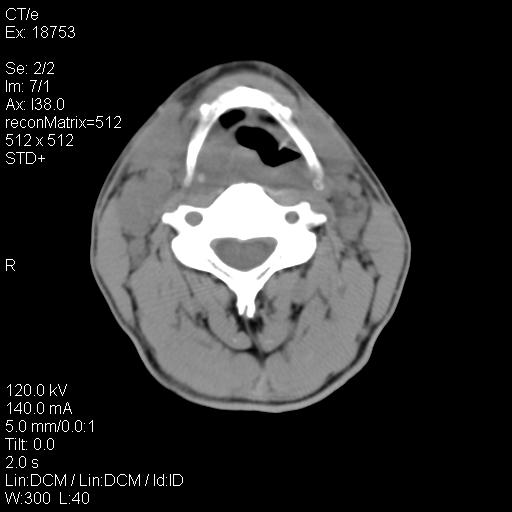

标题: CT21693:男 58岁 右侧咽部疼她2天余 PE:右侧扁桃体肿大 压痛 [打印本页]

标题: CT21693:男 58岁 右侧咽部疼她2天余 PE:右侧扁桃体肿大 压痛

结合病史,考虑感染性病变;建议抗炎治疗复查排除肿瘤性病变。

弥漫性肿胀,与周围组织分界不清,发病急,有明显症状,考虑:感染性病变! 抗炎后复查。

右化脓性扁桃体炎症伴咽后壁脓肿形成.